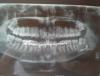

sss111sss Опубликовано 22 сентября, 2012 Поделиться Опубликовано 22 сентября, 2012 Здравствуйте! Очень нужен Ваш совет. Кратко предыстория. Сыну (15 лет) 20.08 сломали челюсть с двух сторон. Слева открытый перелом со смещением. Зашинировали. 28.08 сделали операцию с применением остеосинтеза. 19.09 расшинировали верхнюю челюсть. А рот открывается только на0,5 см. Что может быть? Не придется ли делать повторно? А может это из-за зуба? Снимки высылаю. Заранее огромное спасибо. Ссылка на комментарий

Большой Зеленый Опубликовано 22 сентября, 2012 Поделиться Опубликовано 22 сентября, 2012 Не переживайте все откроется со временем . Повторно ничего делать не придется. Когда все срастется нужно будет удалить 38зуб .Тот что лежит горизонтально. Ссылка на комментарий